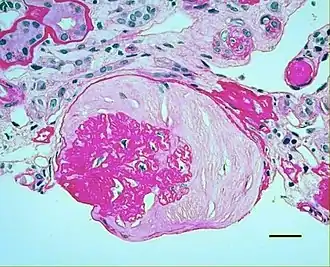

| Micrograph showing renal arterial hyalinosis – pink ring right-of-centre. PAS stain. | |

In the kidneys, as a result of benign arterial hypertension, hyaline (pink, amorphous, homogeneous material) accumulates in the walls of small arteries and arterioles, producing the thickening of their walls and the narrowing of the arterial openings, a process known as arteriolosclerosis. The resulting inadequate blood flow produces tubular atrophy, interstitial fibrosis, and glomerular alterations (smaller glomeruli with different degrees of hyalinization – from mild to sclerosis of glomeruli) and scarring around the glomeruli (periglomerular fibrosis). In advanced stages, kidney failure will occur. Functional nephrons[6] have dilated tubules, often with hyaline casts in the opening of the tubules. Additional complications often associated with hypertensive nephropathy include glomerular damage resulting in protein and blood in the urine.

In benign nephrosclerosis, the changes occurring are gradual and progressive, however, there can be sufficient kidney reserve capacity to maintain adequate kidney function for many years.[10] The large renal arteries exhibit intimal thickening, medial hypertrophy, duplication of the elastic layer. The changes in small arterioles include hyaline arteriolosclerosis (deposition of hyaline, collagenous material), which causes glomerular collapse (wrinkling and thickening of capillary basement membranes and collapse of capillary lumen) and solidification (glomeruli exhibit sclerosis and increase in mesangial matrix). The degree of scarring correlates with the degree of glomerular filtration deficit.